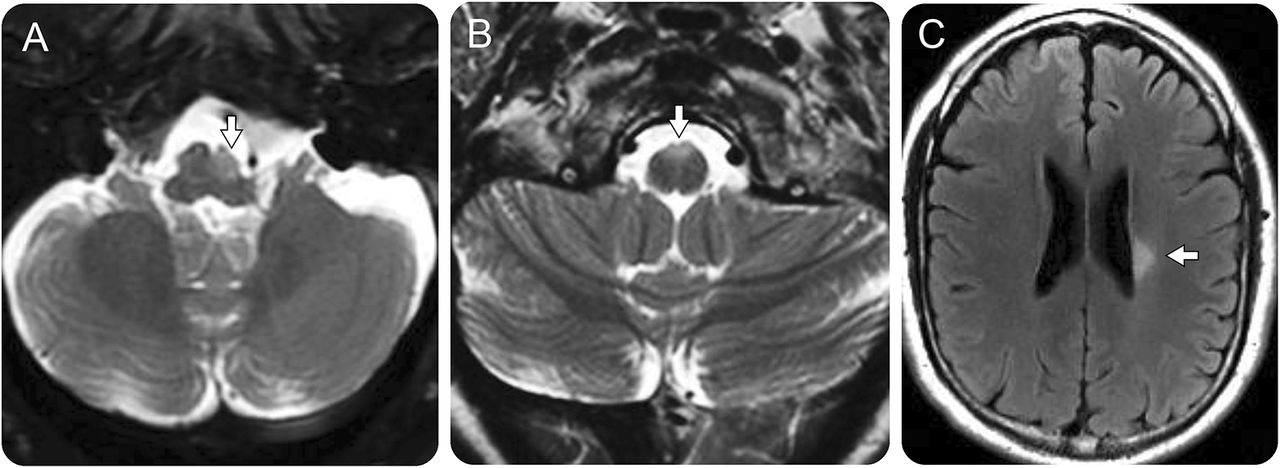

50岁的男人进行性加重了左髓T2-hyperintense nonenhancing病变伴随萎缩在轴向fluid-attenuated反转恢复(天赋)图像(A,箭头)。一个46岁的女人,一个进步的痉挛性的四肢瘫痪被发现有一个nonenhancing T2-hyperintense病变在前面涉及的左翼和右翼金字塔髓质(B,箭头)。一位45岁的人进步的权利(face-sparing)痉挛性轻偏瘫与一个孤独的左室nonenhancing T2-hyperintense病变在轴向天赋图像(C,箭头)。病变并没有改变的MRI随访5年以上(未显示);没有额外的MRI病灶出现了。

孤独的中枢神经系统脱髓鞘病变通常位于颈脊髓或cervico-medullary结(表,图1)。脊髓病变都少于3椎段的长度。局部病灶萎缩与损失的圆形外观的脊髓轴向图像(图1中,B。b, C。b, D.b)是目前在初始成像或开发时间(图2)在21个26(81%)和足够的轴向序列可用;在2例,萎缩导致苹果的外观核心病变(图2 e)与下肢轻瘫或四肢瘫痪。双边病变包括髓金字塔或cervico-medullary结(图3 b)与四肢瘫痪。

孤独的脊髓病变的平均宽度是5.5×4毫米(范围出)和平均长度是18毫米(范围7-52)。2 27例(7%),钆增强孤独的脊髓损伤的初始图像,随后解决(图2)。非特异性脑白质MRI T2 hyperintensities共存8例(27%)。